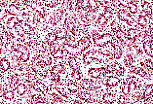

男性生殖系统